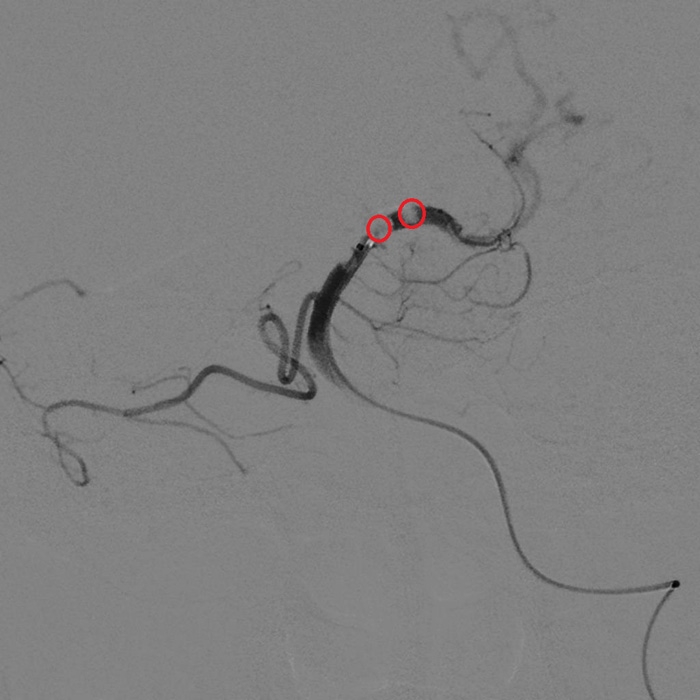

微導(dǎo)管造影顯示血栓(紅圈處)

??? 22:10? 王大伯病情進(jìn)一步加重,神經(jīng)外科戴偉民主任醫(yī)師團(tuán)隊(duì)、麻醉師和介入室的醫(yī)護(hù)人員全部已經(jīng)到位。全腦血管造影顯示栓塞部位在基底動(dòng)脈末端,雙側(cè)小腦上動(dòng)脈及雙側(cè)大腦后動(dòng)脈開口處完全閉塞。

手術(shù)前血管造影提示雙側(cè)小腦上動(dòng)脈及雙側(cè)大腦后動(dòng)脈開口處完全閉塞

取栓后造影顯示雙側(cè)小腦上動(dòng)脈及雙側(cè)大腦后動(dòng)脈充盈良好